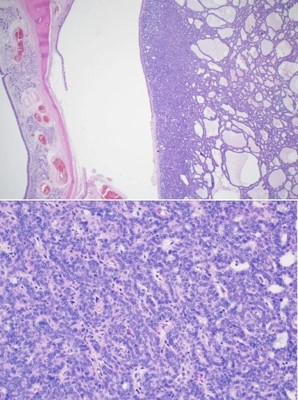

The patient was seen in an outpatient setting for a two week follow-up and discussion of final pathology results. These showed two masses: ameloblastoma with the invasion of the hard palate, posterior maxilla, and maxillary sinus (Figure 5) as well as a SCC with the cartilaginous and bony invasion of the nasal septum and nasal bone (Figure 6). During this clinic visit, he reported some discharge from one of the incisions and flap edema. He was otherwise doing well, with significant improvements in dysphagia and nasal obstruction. The flap adhered well to native tissue and appeared healthy. The infection cleared up over the next two weeks on a course of antibiotics, and the patient’s nasogastric tube was removed within the following three weeks.

Figure 5: Photomicrographs of final pathological examination of the tumor showing ameloblastoma with the bony invasion of the hard palate (top) and proliferating nest cells (bottom).